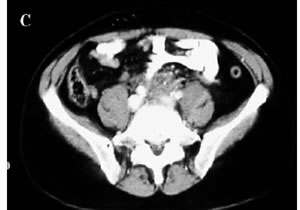

Figura 1. A-C: Tc spirale con MdC; evidenza di tessuto fibroso in sede retroperitoneale disposto attorno all'aorta,alla vena cava inferiore e alla biforcazione iliaca.(Da referenza 30)